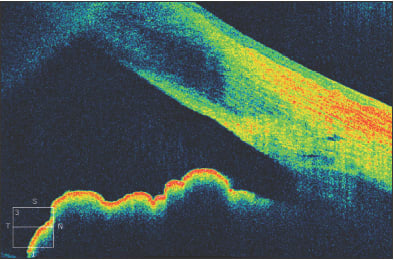

In Figure 5, a 45-year-old man is seen to have iridolenticular synechiae and an anterior polar cataract, using ASOCT. The anterior chamber angle can be identified, and these high resolution images often allow the identification of Schlemm's canal (Figure 6).

Figure 5. Anterior segment OCT demonstrating iridolenticular apposition and an anterior polar cataract.

Figure 6. The anterior chamber angle in a patient with a narrow, but non-opposed, angle. Schlemm's canal can be visualized.